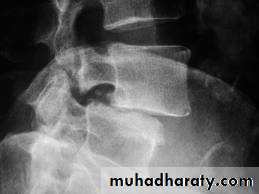

6.Spondylolisthesis